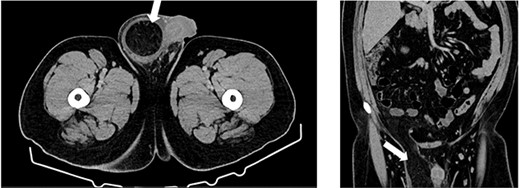

Computed tomography (CT) axial and coronal imaging showing large fat-containing right inguinal hernia (white arrow).